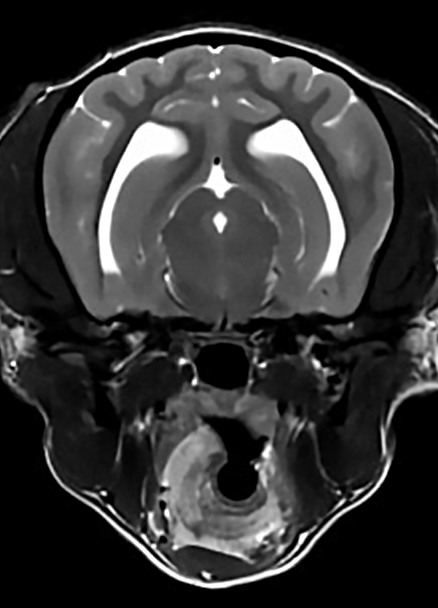

본 병원은 GE사의 1.5T 고해상도 자기공명영상장치(MRI)를 이용하여, 자기장을 이용한 비침습적 방식으로 뇌, 척수, 근골격계 등 다양한 연부조직을 정밀하게 영상화할 수 있습니다. MRI는 방사선을 사용하지 않아 반복 촬영에도 안전하며, 신경계 및 연부조직에 대한 탁월한 해상도를 제공하여 정확한 진단에 매우 유용합니다.

또한 본원의 MRI 장비는 GE사의 PROPELLER 기법을 도입하여 호흡이나 움직임에 따른 영상 왜곡을 최소화하면서도 검사 시간을 단축시켜, AI 기반 영상 처리 기술을 통해 노이즈를 줄이고 더욱 선명하고 명확한 영상을 획득할 수 있습니다. 이러한 기술적 강점을 바탕으로 마취 시간과 그에 따른 환자의 부담을 줄이면서도, 진단에 충분한 고화질 영상을 안정적으로 확보할 수 있습니다.